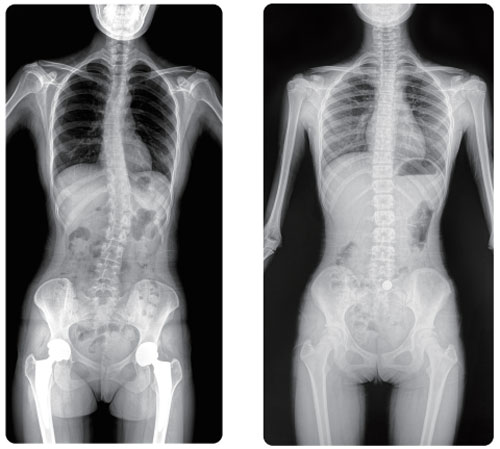

The 17**34″ large view FPD, which is twice as big as the classical 17**17″ panel on the market, can obtain an image without further stitching. Compared with the conventional DR requiring multiple stitching, PLX8600 solve the issues caused by stitching such as uneven image density, image registration and magnification provide a true clinical solution of large view image.

Thanks to rapid exposure of PL X8600 large view dynamic FPD DRF system, patients are able to finish the examination faster, and receive only 1/2 or 1/3 radiation of the conventional DR requiring multiple stitching in a single exposure.

Weight-bearing is the amount of weight a patient puts on an injured body part, it reveals the pathological condition of the whole body skeleton in naturally standing. Fast imaging a 1:1 precise full spine image in a weight-bearing position.

PLX8600 is also capable of showing clear dynamic image of multi-angle in weight-bearing position, revealing healing condition of lesions more specifically, bringing more perspectives for clinical examination and high-resolution DSI.

Full spine in one image No additional stitching required

The idea of full spine in one exposure has a significant value in the clinical usage of lumbar degenerative diseases, ankylosing spondylitis, spinal tuberculosis etc.

Giving a thorough examination of fracture site under the fluoroscopy image, as well as performing preoperative and postoperative diagnosis. E.g. oblique position of spine, pars interarticularis etc.

Observing the whole spinal motion through fluoroscopy, as well as mobility and bone structure of pathological spine. Guided by fast DSI to capture keyframes, enabling radiologist to deploy precise surgical plans.